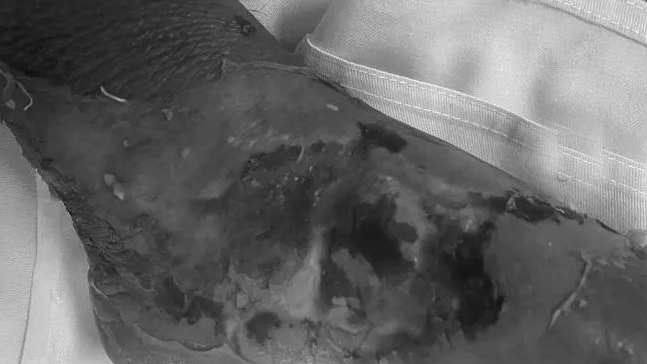

Đặc biệt, sau khi bị thương, người bệnh đã được người nhà nhai lá cây và tự ý đắp vào tổn thương theo kinh nghiệm dân gian khiến cho vết thương tiềm ẩn nguy cơ nhiễm trùng, hoại tử gây nguy hiểm cho người bệnh.

ThS.BS Nguyễn Phú Tiến – Khoa Phẫu thuật Chấn thương chỉnh hình, Bệnh viện E cho biết, người bệnh nhập viện trong tình trạng xuất hiện vết thương vùng cẳng tay, ngón I và III bàn tay phải do tai nạn sinh hoạt. Vết thương xuất hiện dịch đục, tấy đỏ quanh mép vết thương, có nhiều dị vật lá cây được đắp trên vết thương.

Khai thác tiền sử bệnh án, người bệnh bị thương do mảnh kính vỡ rơi vào tay nhưng thay vì đến bệnh viện, người nhà lại áp dụng các phương thức dân gian: nhai, đắp lá cây không rõ nguồn gốc hoặc bôi mật gấu, rượu ngâm… với hy vọng người bệnh sẽ khỏi. Tuy nhiên sau khi sử dụng các phương pháp dân gian trên, vết thương không những không thuyên giảm mà còn tiến triển nặng hơn. Vết thương chảy mủ, sưng nề, tiềm ẩn nguy cơ nhiễm trùng, hoại tử, cơ co cứng, khó vận động… Lúc này, gia đình mới vội vàng đưa người bệnh đến Bệnh viện E để kiểm tra, điều trị.